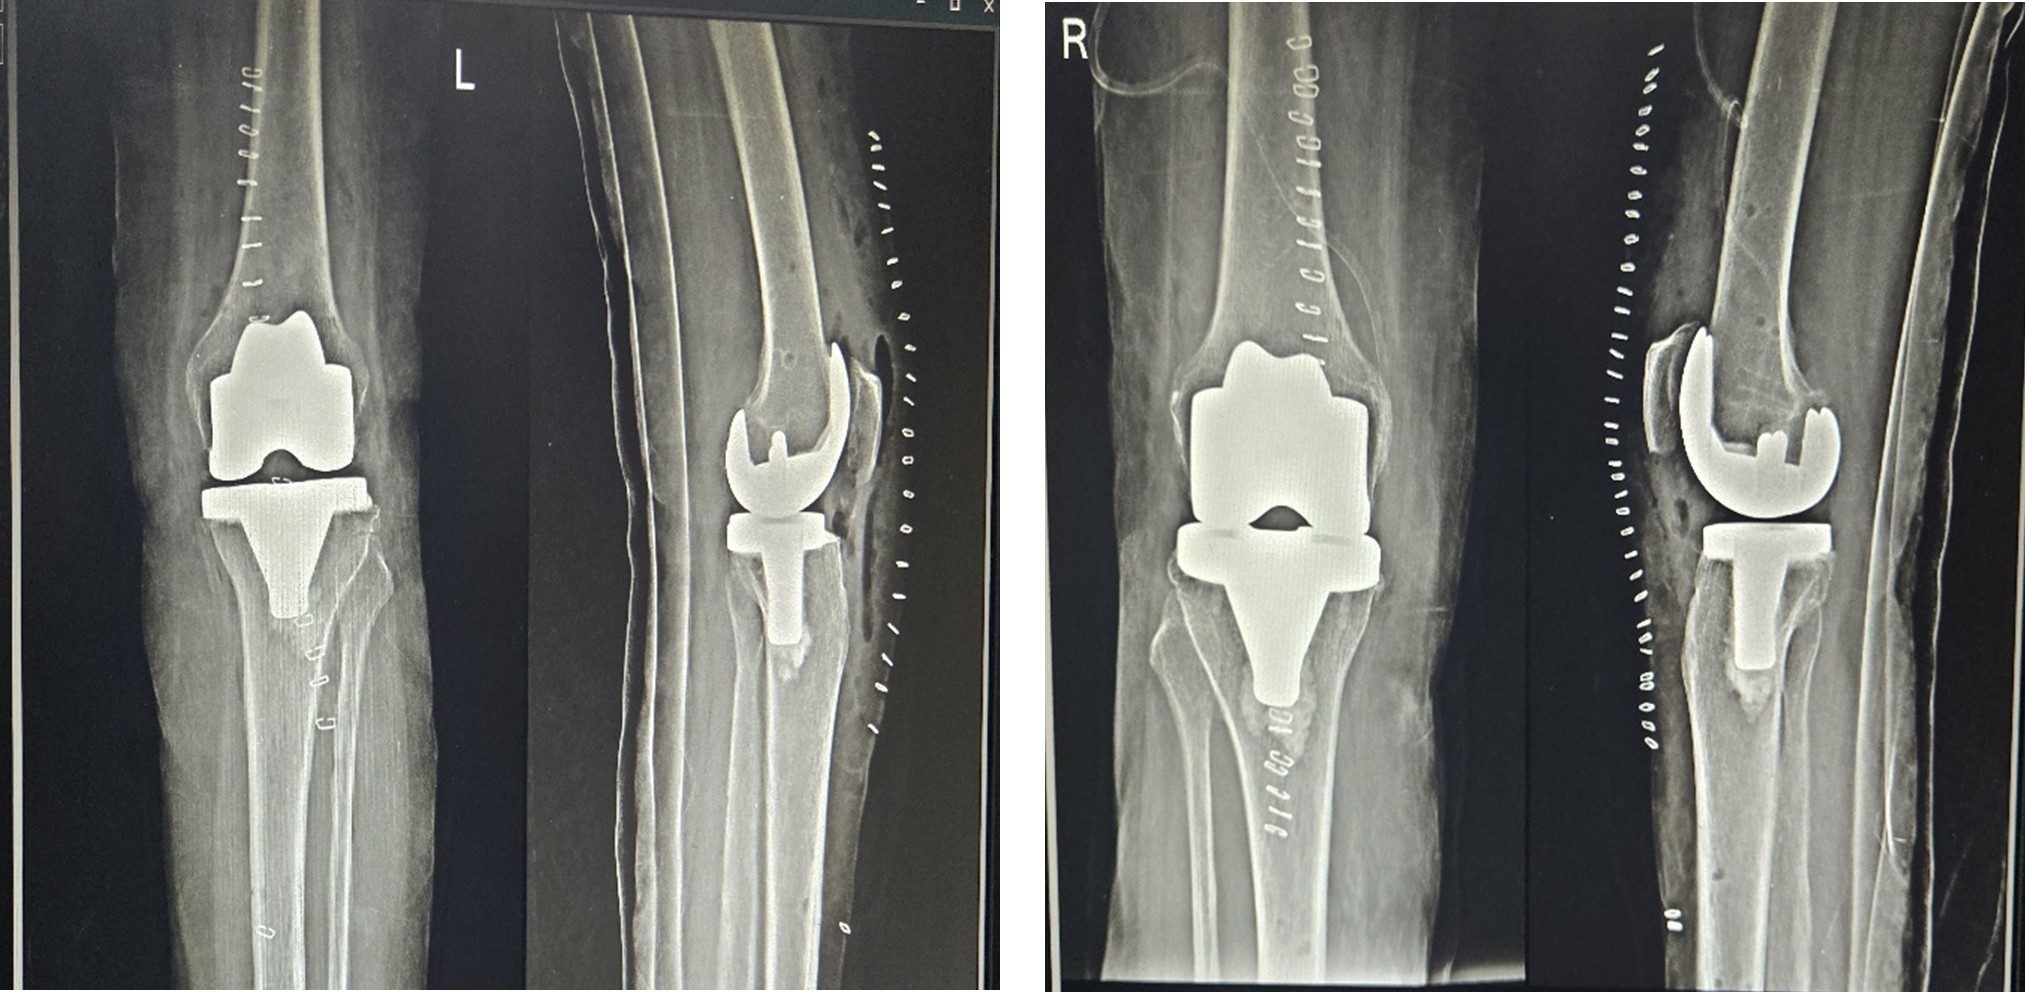

Postoperative X-ray

- Case presentation on Total Knee Replacement